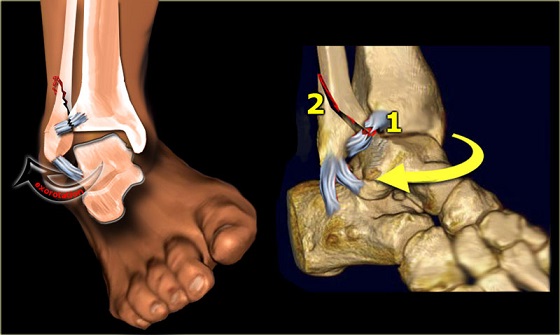

• mechanism includes avulsion or shearing force • risk of instability. Dorsal cortical fractures without evidence of instability.

Commonly caused by a twisting force (usually eversion) applied to the foot resulting in increased tension on posterior tibial. Caused by a compression injury i.e the bottom of the tibia smashing downward into the top of the talus or vice a versa.the joint is. Segond fracture associated with increased probability of other soft tissue such as acl rupture; They may be divided into 1) high energy trauma fracture, 2) fatigue fracture from cyclical and sustained mechanical stress. Focal disruption of the cortical bone ultimatly leads to osteophyte growth. Vertebral fracture and cortical bone changes in. What is a cortical fracture? What is a cortical fracture? Modelling and stress remodelling of the dorsal cortex of the third metatarsal bone occur in young racehorses but, unlike in the third metacarpal bone. Fractures of the proximal sesamoid bones in horses. Disruption and periosteal tearing on convex side of bone, with intact periosteum on concave side of fx. We found one dictionary with english definitions that includes the word cortical fracture: Hip fractures and the contribution of cortical versus trabecular bone to femoral neck strength. Cortical avulsion fracture is the most common type of navicular fracture. John kiel on 30 june 2019 19:53:38. Radiographically, occult and subtle fractures are a diagnostic challenge. Cortical biopsies from atypical fracture patients show increased cortical thickness and reduced intracortical bone volume fraction compared with those from typical fracture patients.